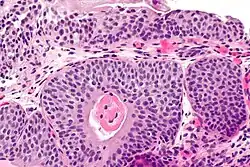

| Micrograph showing cystitis cystica. | |